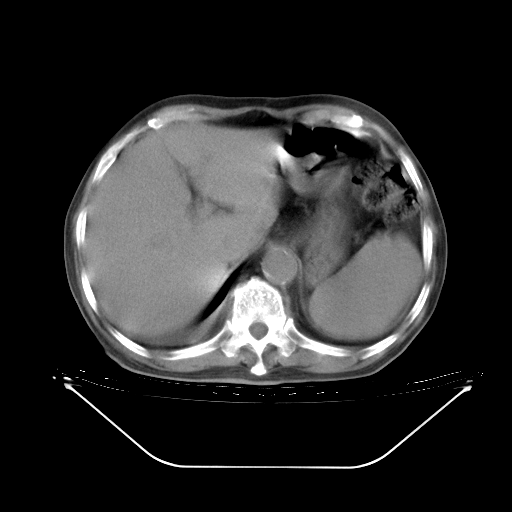

胸腹部CT,诊断意见:左上肺叶钙化灶、左侧胸膜局限性增厚并钙化、胆囊炎。描述部分肺组织呈磨玻璃样改变。

5月9日肺部CT(在4月27日齐鲁医院肺部CT描述部分肺组织磨玻璃样改变,12天后肺组织广泛磨玻璃样改变)